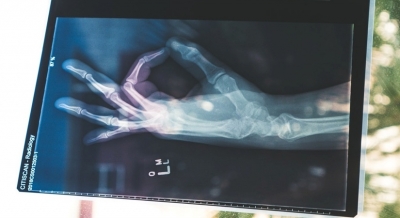

Bone trouble?

(life) Solid physical ability and performance primarily results from strong bone health. Weaker bones may delay desired physical outcomes, physical milestones, and put a person at risk of sustaining serious injuries.

It is often perceived that Osteoporosis is an issue of the 'seniors', and that it is not something one must worry about in the early ages. Although it is true that most hip, spine and forearm fractures are likely to be seen in the elderly (people of 40- 65yrs), if you experience a fracture, and also show symptoms of Osteoporosis, it may be too late to reverse the onset of the condition. It is therefore imperative to pay attention to bone health, especially if you have been diagnosed with the bone disease